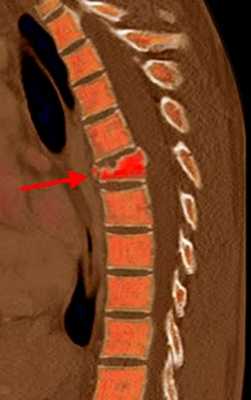

МРТ позвоночника. Т2-взвешенная сагиттальная МРТ. Компрессионный перелом. Цветовая обработка изображения.

Компрессионные переломы относятся к наиболее частым повреждениям позвонков, составляют около 90% травм позвоночника. Типичными проявлениями при МРТ позвоночника является клиновидность переднего отдела тела позвонка и нарушение замыкательной пластинки. Отсутствие повреждение в задних отделах по данным МРТ отличает простой компрессионный перелом от более тяжелого взрывного. При простом компрессионном переломе часто наблюдается выбухание заднего отдела назад с сужением позвоночного канала.

Компрессионные переломы видны при рентгенографии, однако уже при наличии заметной клиновидности. На КТ лучше видны дефекты замыкательной пластинки. МРТ позвоночника отличается возможностью определять «свежие» компрессионные переломы, сопровождающиеся нарушением трабекул и отеком костного мозга.

КТ и МРТ грудного отдела позвоночника. Множественные компрессионные переломы (стрелки).